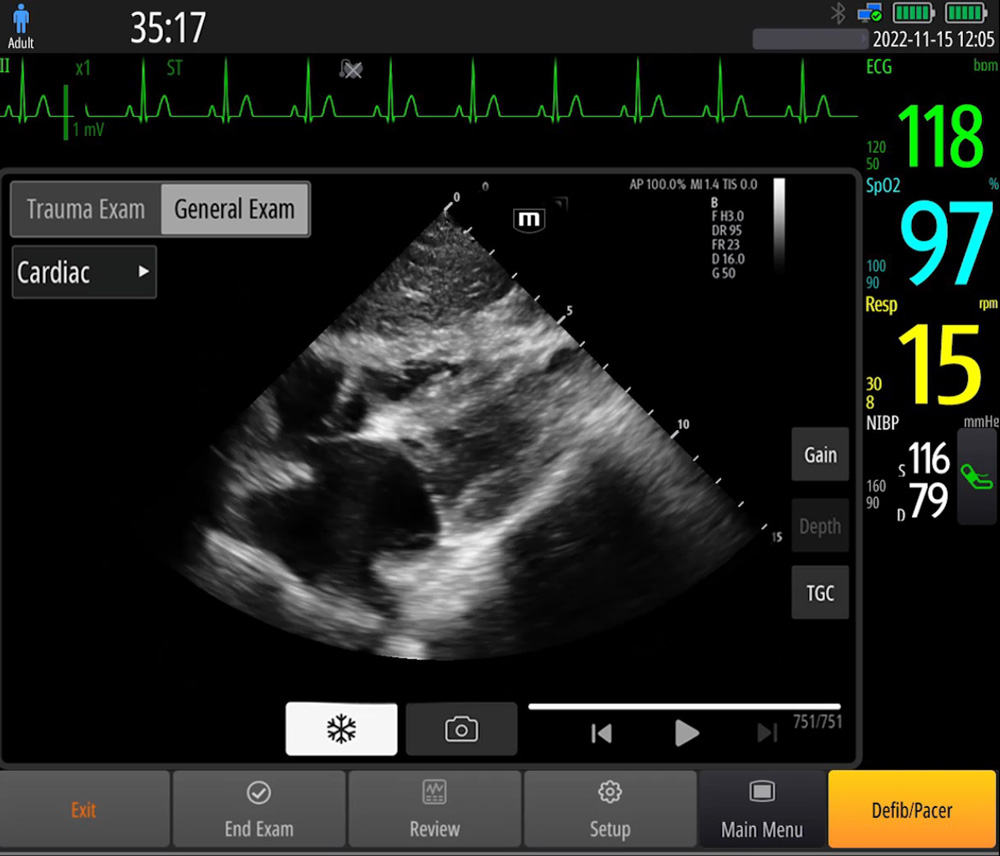

EcografÃa en el punto de atenciÃģn (POCUS)

Las funciones integradas de ecografÃa fundamentan el diagnÃģstico in situ, con una guÃa de operaciÃģn inteligente para facilitarlo.

- ImÃĄgenes de referencia y guÃas de operaciÃģn

- Sonda de matriz en fase: alta resoluciÃģn, ampliamente utilizada